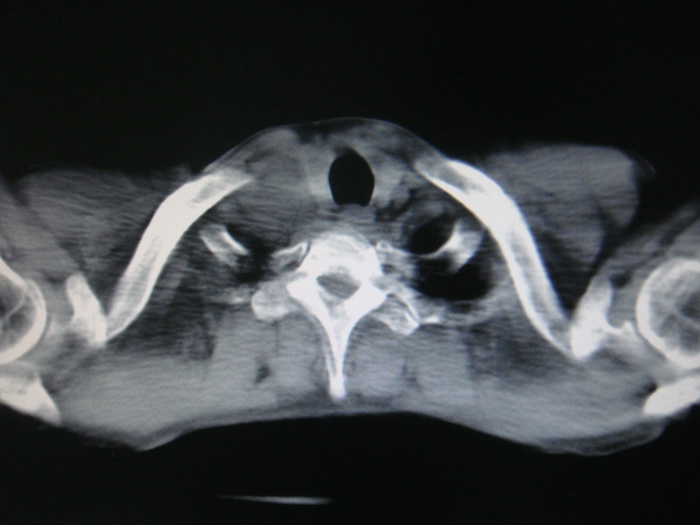

标题: CT28366:男性,45岁,偶尔发现右颈部肿块行胸部CT扫描。 [打印本页]

男性,45岁,偶尔发现右颈部肿块行胸部ct扫描。

两肺多发结节灶及纵膈淋巴结肿大考虑为转移

两肺多发性转移瘤,纵隔淋巴结转移。

两肺多发性转移瘤,前上纵隔淋巴结转移。